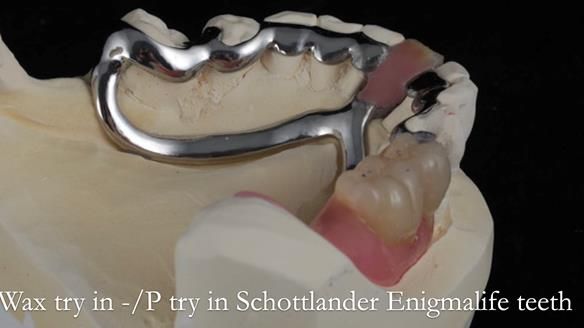

Welcome to my Newsletter 54 showing the making and fitting of dentures (a complete upper metal reinforced denture, a lower immediate partial denture and a definitive Scandinavian designed, metal based lower partial denture) for David, a 75 -year-old man. The full protocol workflow is presented including the use of dentate photographs to mimic his natural teeth.

The clinical situation and treatment process is shown in detail below. I provided the clinical work. Rowan Garstang, my dental technician, provided the technical work.